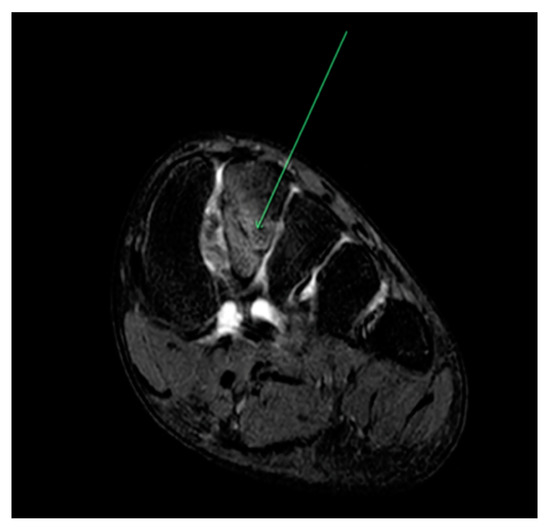

| Metatarsal (Figure 1) | Running (athletics) [20] Gymnastics [27] Basketball [21,30] Volleyball [15] Ballet [17,31,32] |